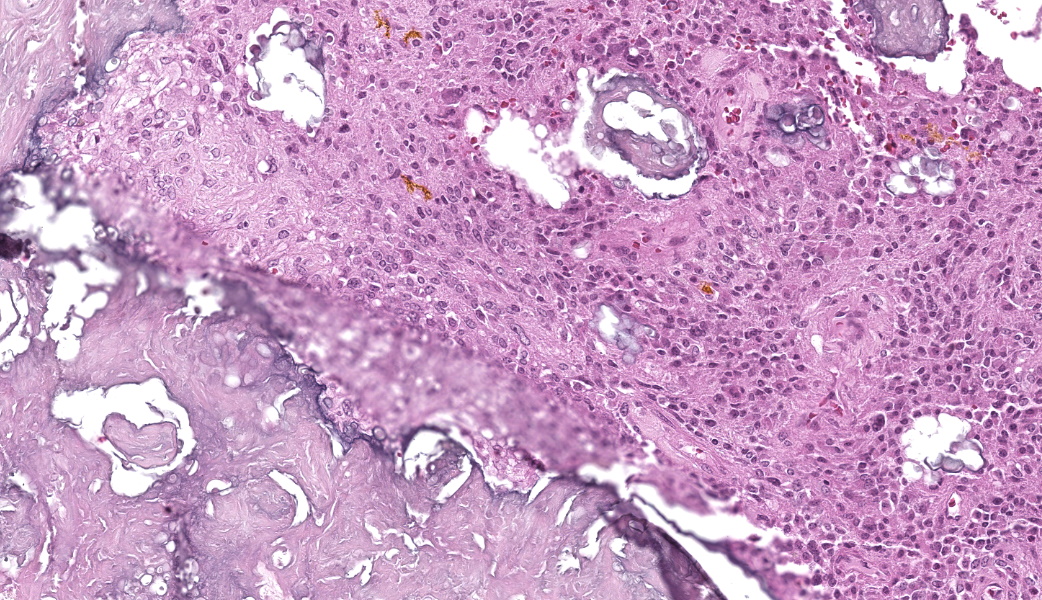

The affected skeletal muscle and subcutis were infiltrated and expanded by abundant, irregular, globoid amphophilic to basophilic material, consistent with mineralization. This mineralized material was surrounded by extensive fibrous connective tissue proliferation (fibrosis), admixed with numerous macrophages, lymphocytes, and fewer multinucleated giant cells containing phagocytosed mineral material. Scattered throughout the mass, rare foci of osteoid formation were observed, characterized by a low number of empty lacunae and necrotic osteoids undergoing remodeling. Multifocally within the mineralized soft tissue lesions, multiple tortuous blood vessels with thickened tunica media were observed. Additionally, there were areas of extensive hemorrhage, neovascularization, and granulation tissue formation infiltrating and replacing the surrounding adipose tissue.

In this case, the lesions were confined to the right pelvic limb, with no evidence of involvement of other organ systems. A diagnosis of calcinosis circumscripta (tumoral calcinosis) was established based on the morphological, histopathological and immunohistochemical characteristics of the lesion. Mason trichrome, Von Kossa and Perl's Prussian blue stains were performed and were positive for the fibrous connective tissue (the first one) and the globular amorphous mineral (the last two). The presence of iron within the mineralized material is intriguing. Anecdotally, the African Green Monkeys on this facility tend to present hepatic iron overload and multifocal organ hemosiderosis. Extraskeletal osteosarcoma was considered as a potential differential. However, the cellular infiltrate was immunopositive for IBA-1 (histiocytes/macrophages) and immunonegative for SATB2 (osteoblastic origin, osteosarcoma), alpha-SMA38 (mature myofibroblast, smooth muscle tumor), SOX10 (neural crest origin, melanoma and certain soft tissue neoplasms), and S100 (amelanotic melanoma and certain soft tissue neoplasms). Based on clinical history of this animal, the lesion in this case most likely represents dystrophic calcification secondary to prior traumatic injury, as has been described in other nonhuman primates. To date, neither metastatic nor idiopathic calcification has been reported in this species.

A valuable discussion was held on the functional differences between M1 and M2 macrophages and the role of CD4+ T-helper cells in driving this differentiation. M1 macrophages, associated with pro-inflammatory responses, express CD68 and CD80, whereas M2 macrophages, associated with tissue repair and remodeling, express CD163 and CD206. Dr. Alves? lab ran these markers for this case, and the immunophenotype confirmed a predominance of M2 macrophages within the lesion. This finding aligned well with the chronicity of the process and the extensive remodeling present.